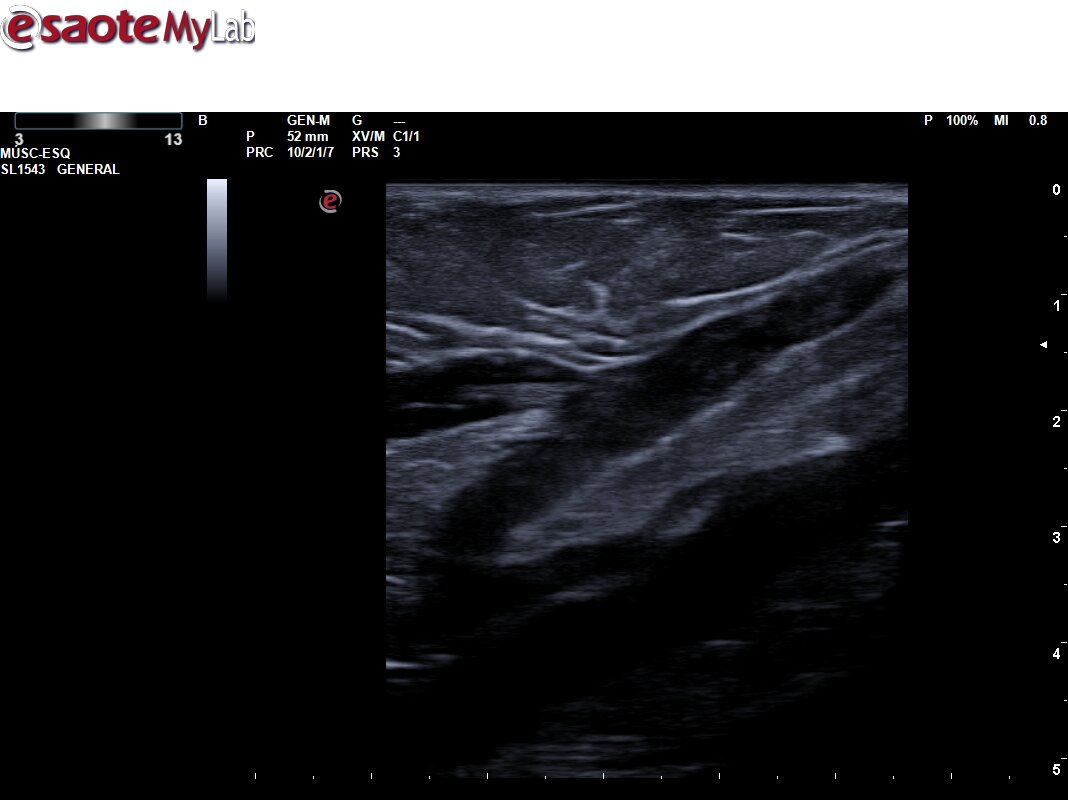

Ecografía primaria: Se explora sistema venoso profundo de MII presentando completa compresibilidad y Doppler + en la exploración extendida, así como ausencia de contenido ecogénico. Se amplía estudio a sistema superficial, apreciándose a nivel de Safena menor contenido hiperecogénico en una extensión superior a 5 cm, próximo a la desembocadura en vena poplítea. Ausencia de compresibilidad.

Ecografía urgencias: Se explora sistema venoso profundo de MII no apreciándose signos de trombosis. Sistema venoso profundo compresible, permeble a flujo fásico con movimientos respiratorios y maniobras de compresión. Vena safena menor izquierda no compresible, aumentada de calibre y con contenido ecogénico en todo su trayecto. Hallazgos compatibles con tromboflebitis superficial extensa.